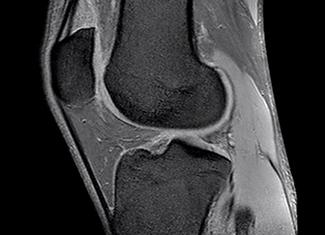

Мрт локтевого сустава

МРТ локтевого сустава: что показывает и как делают?

Этот диагностический метод имеет массу преимуществ, поэтому широко применяется во всех сферах медицины. Сущность МРТ заключается в воздействии магнитным полем на локтевой сустав и получении резонанса в виде радиосигналов.

МРТ локтевого сустава дает возможность получить точный результат исследования таких структур дистальной части плеча и проксимальной части предплечья: